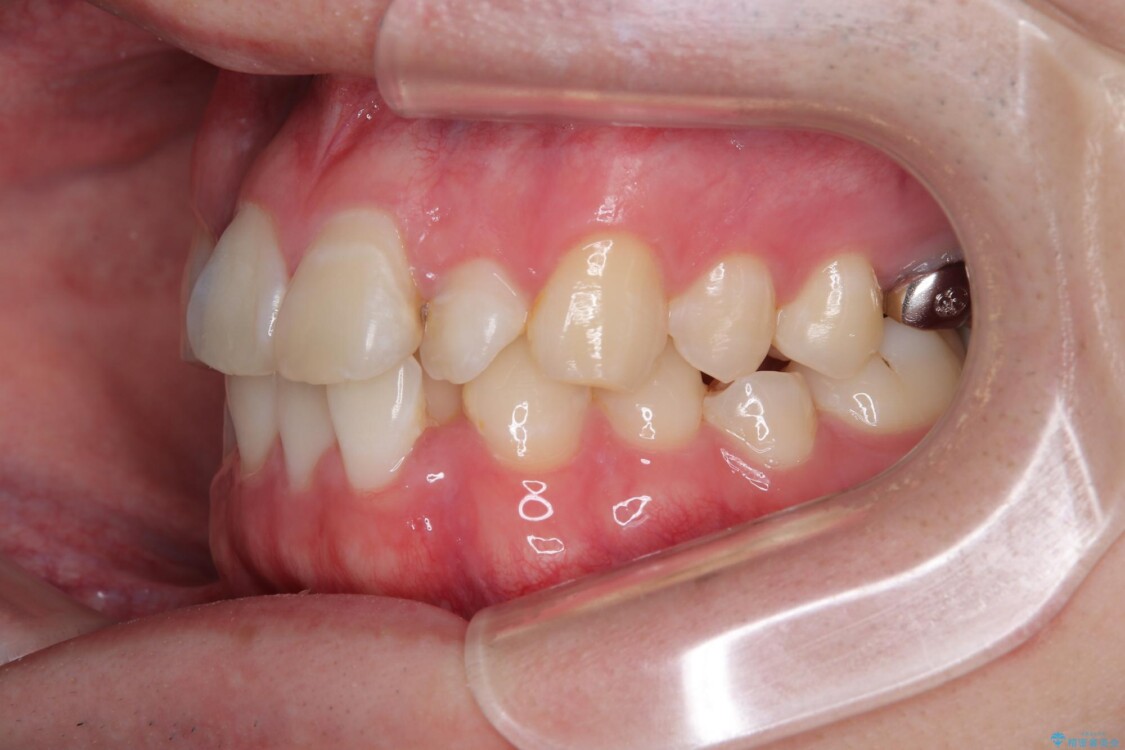

初診時の状態

・上下ともに歯がきれいに並びきらず、がたつきが見られました。

・上下の前歯の中心(正中)がずれています。

・特に上顎の幅が狭いため、下顎の歯列も内側に入り込み、歯が並ぶスペースが不足していました。

治療前

• 1年でここまで変わる!歯列のがたつきと正中のズレを改善した矯正治療(メタルブラケット×MARPE) 治療前画像